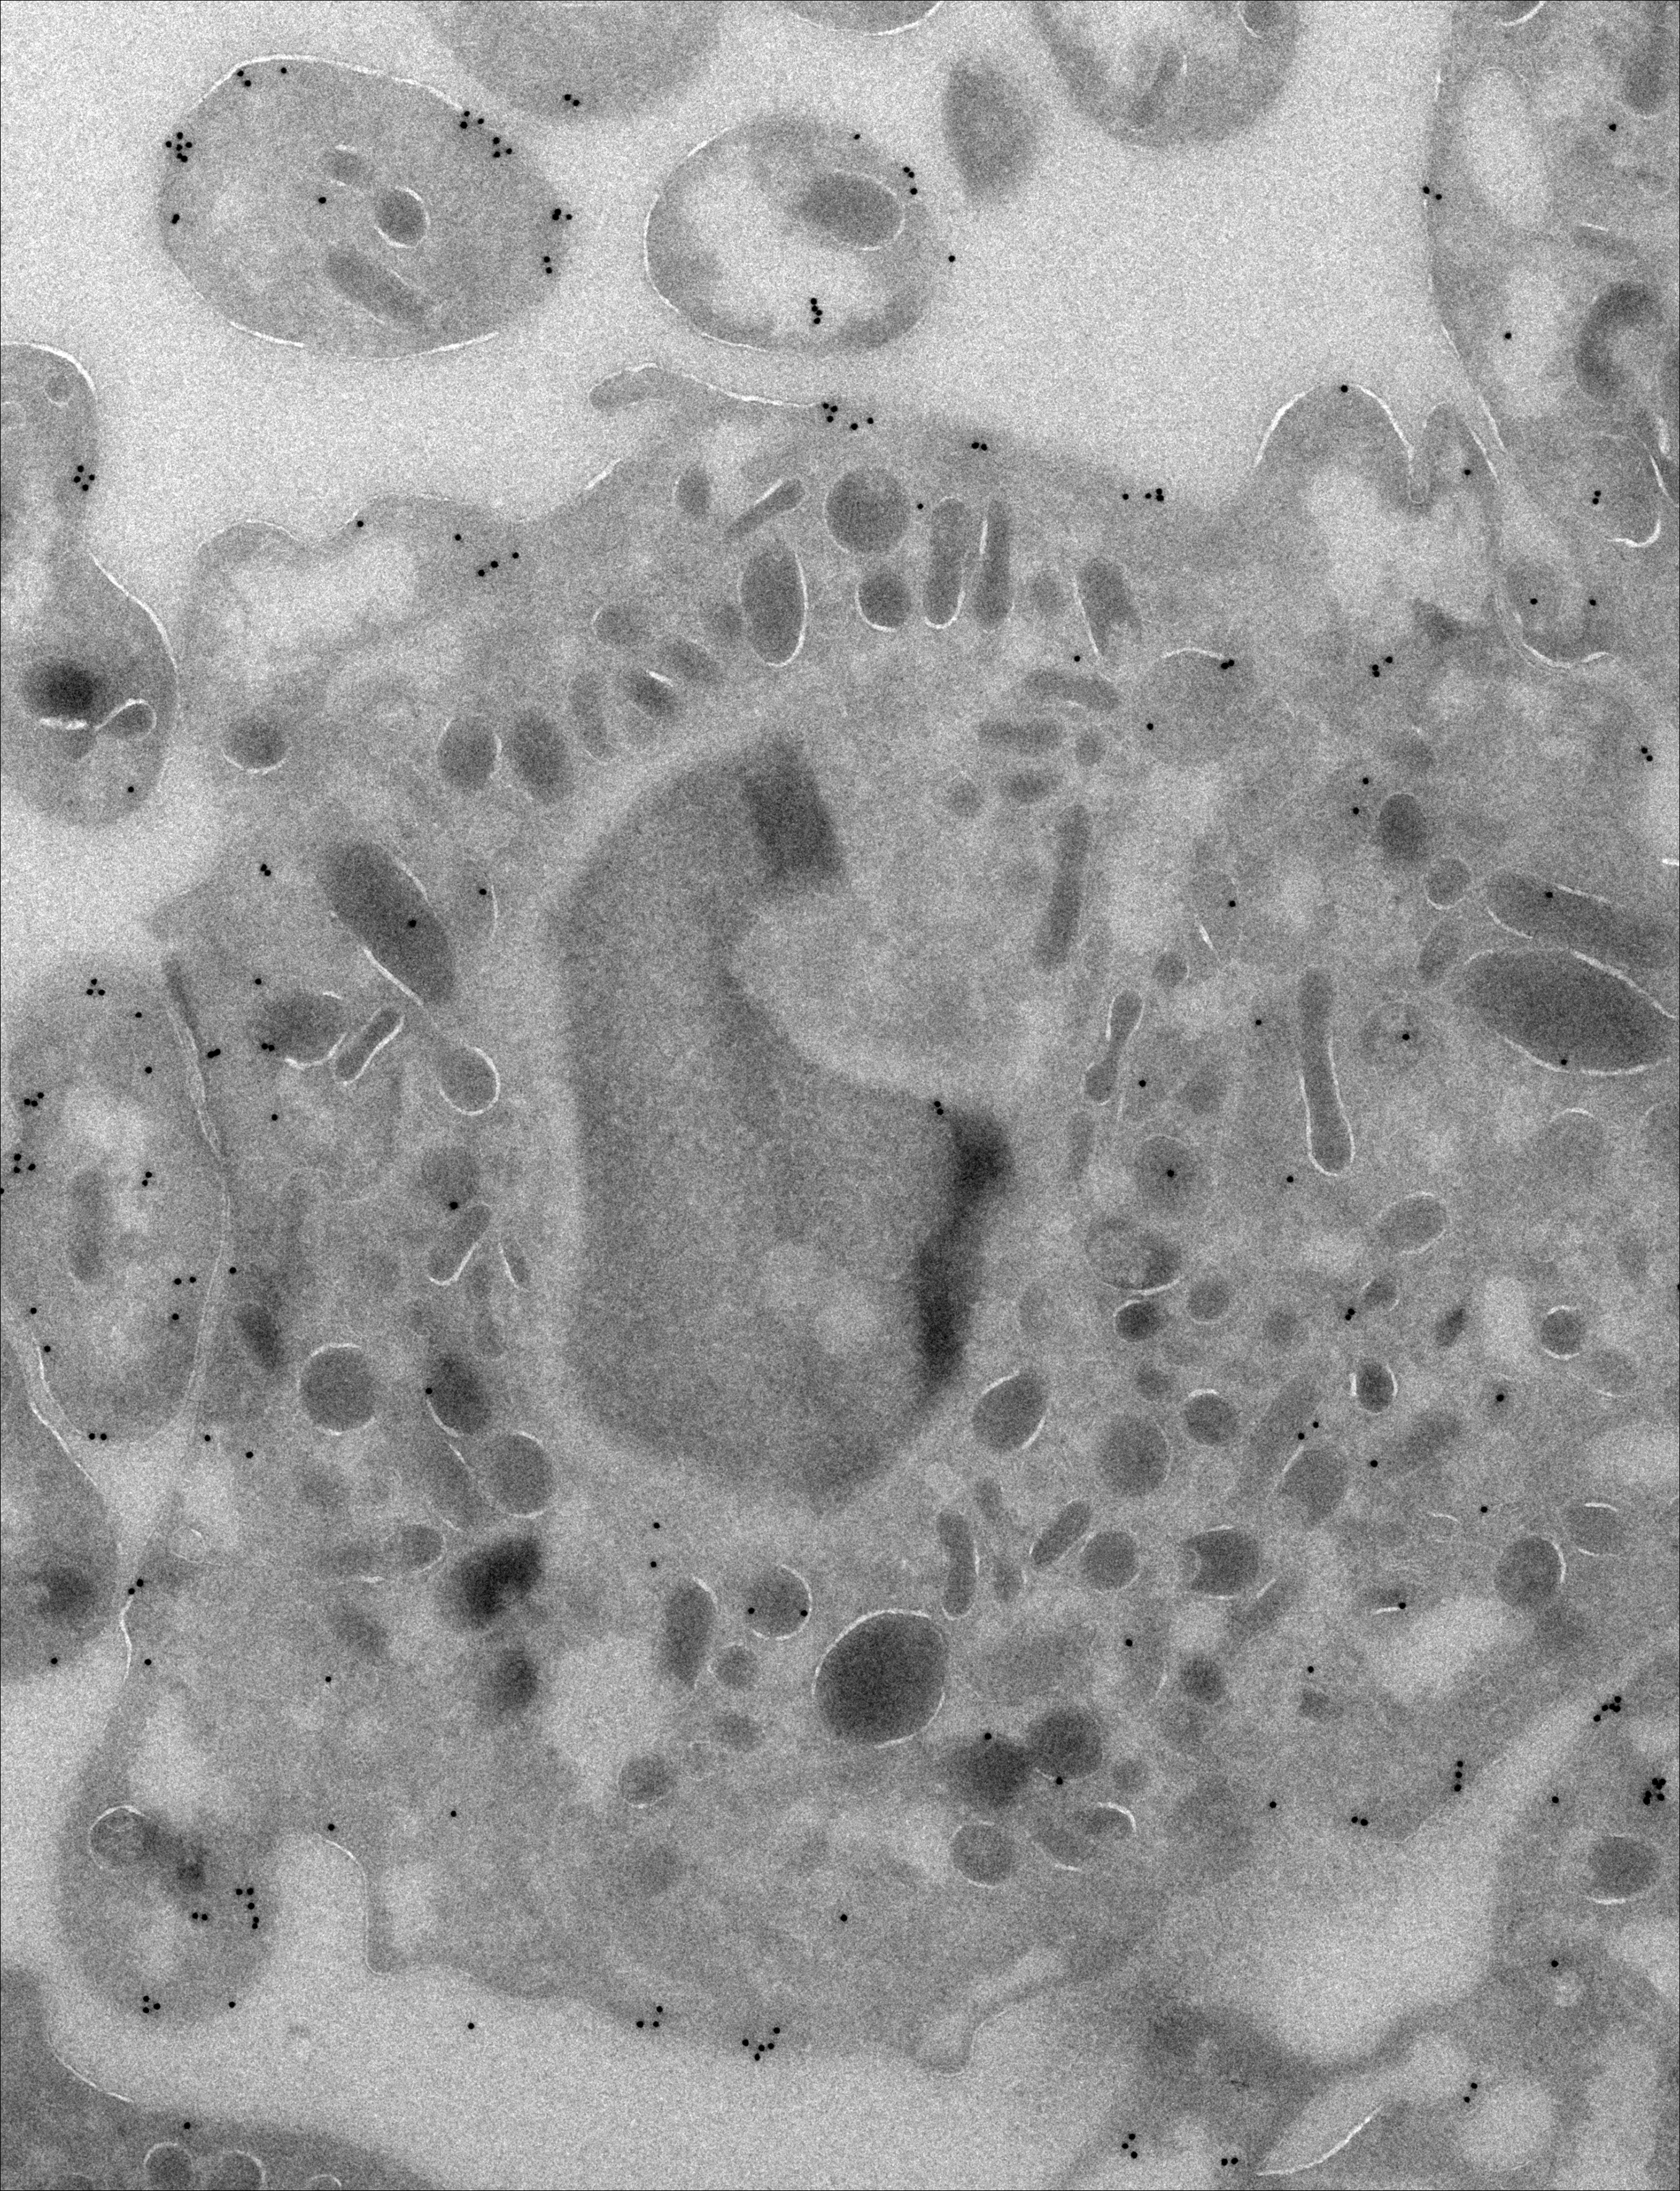

Immunoelectron microscopy image stained for antiactin (black dots) from a primary neutrophil from an MKL1-deficient patient. In addition to reduced actin content, MKL1-deficient neutrophils had blunted pseudopodia in comparison with control neutrophils. See the article by Sprenkeler et al on page 2171.

MKL1 deficiency results in a severe neutrophil motility defect due to impaired actin polymerization

Megakaryoblastic leukemia 1 (MKL1) is a widely expressed transcription factor that is important for actin polymerization. Through study of 2 siblings with primary immunodeficiency due to MKL1 deficiency, the authors demonstrated a profound defect in neutrophil motility. Interestingly, fibroblasts had normal migratory properties, likely due to compensation with a closely related MKL2 protein that is not expressed in neutrophils.